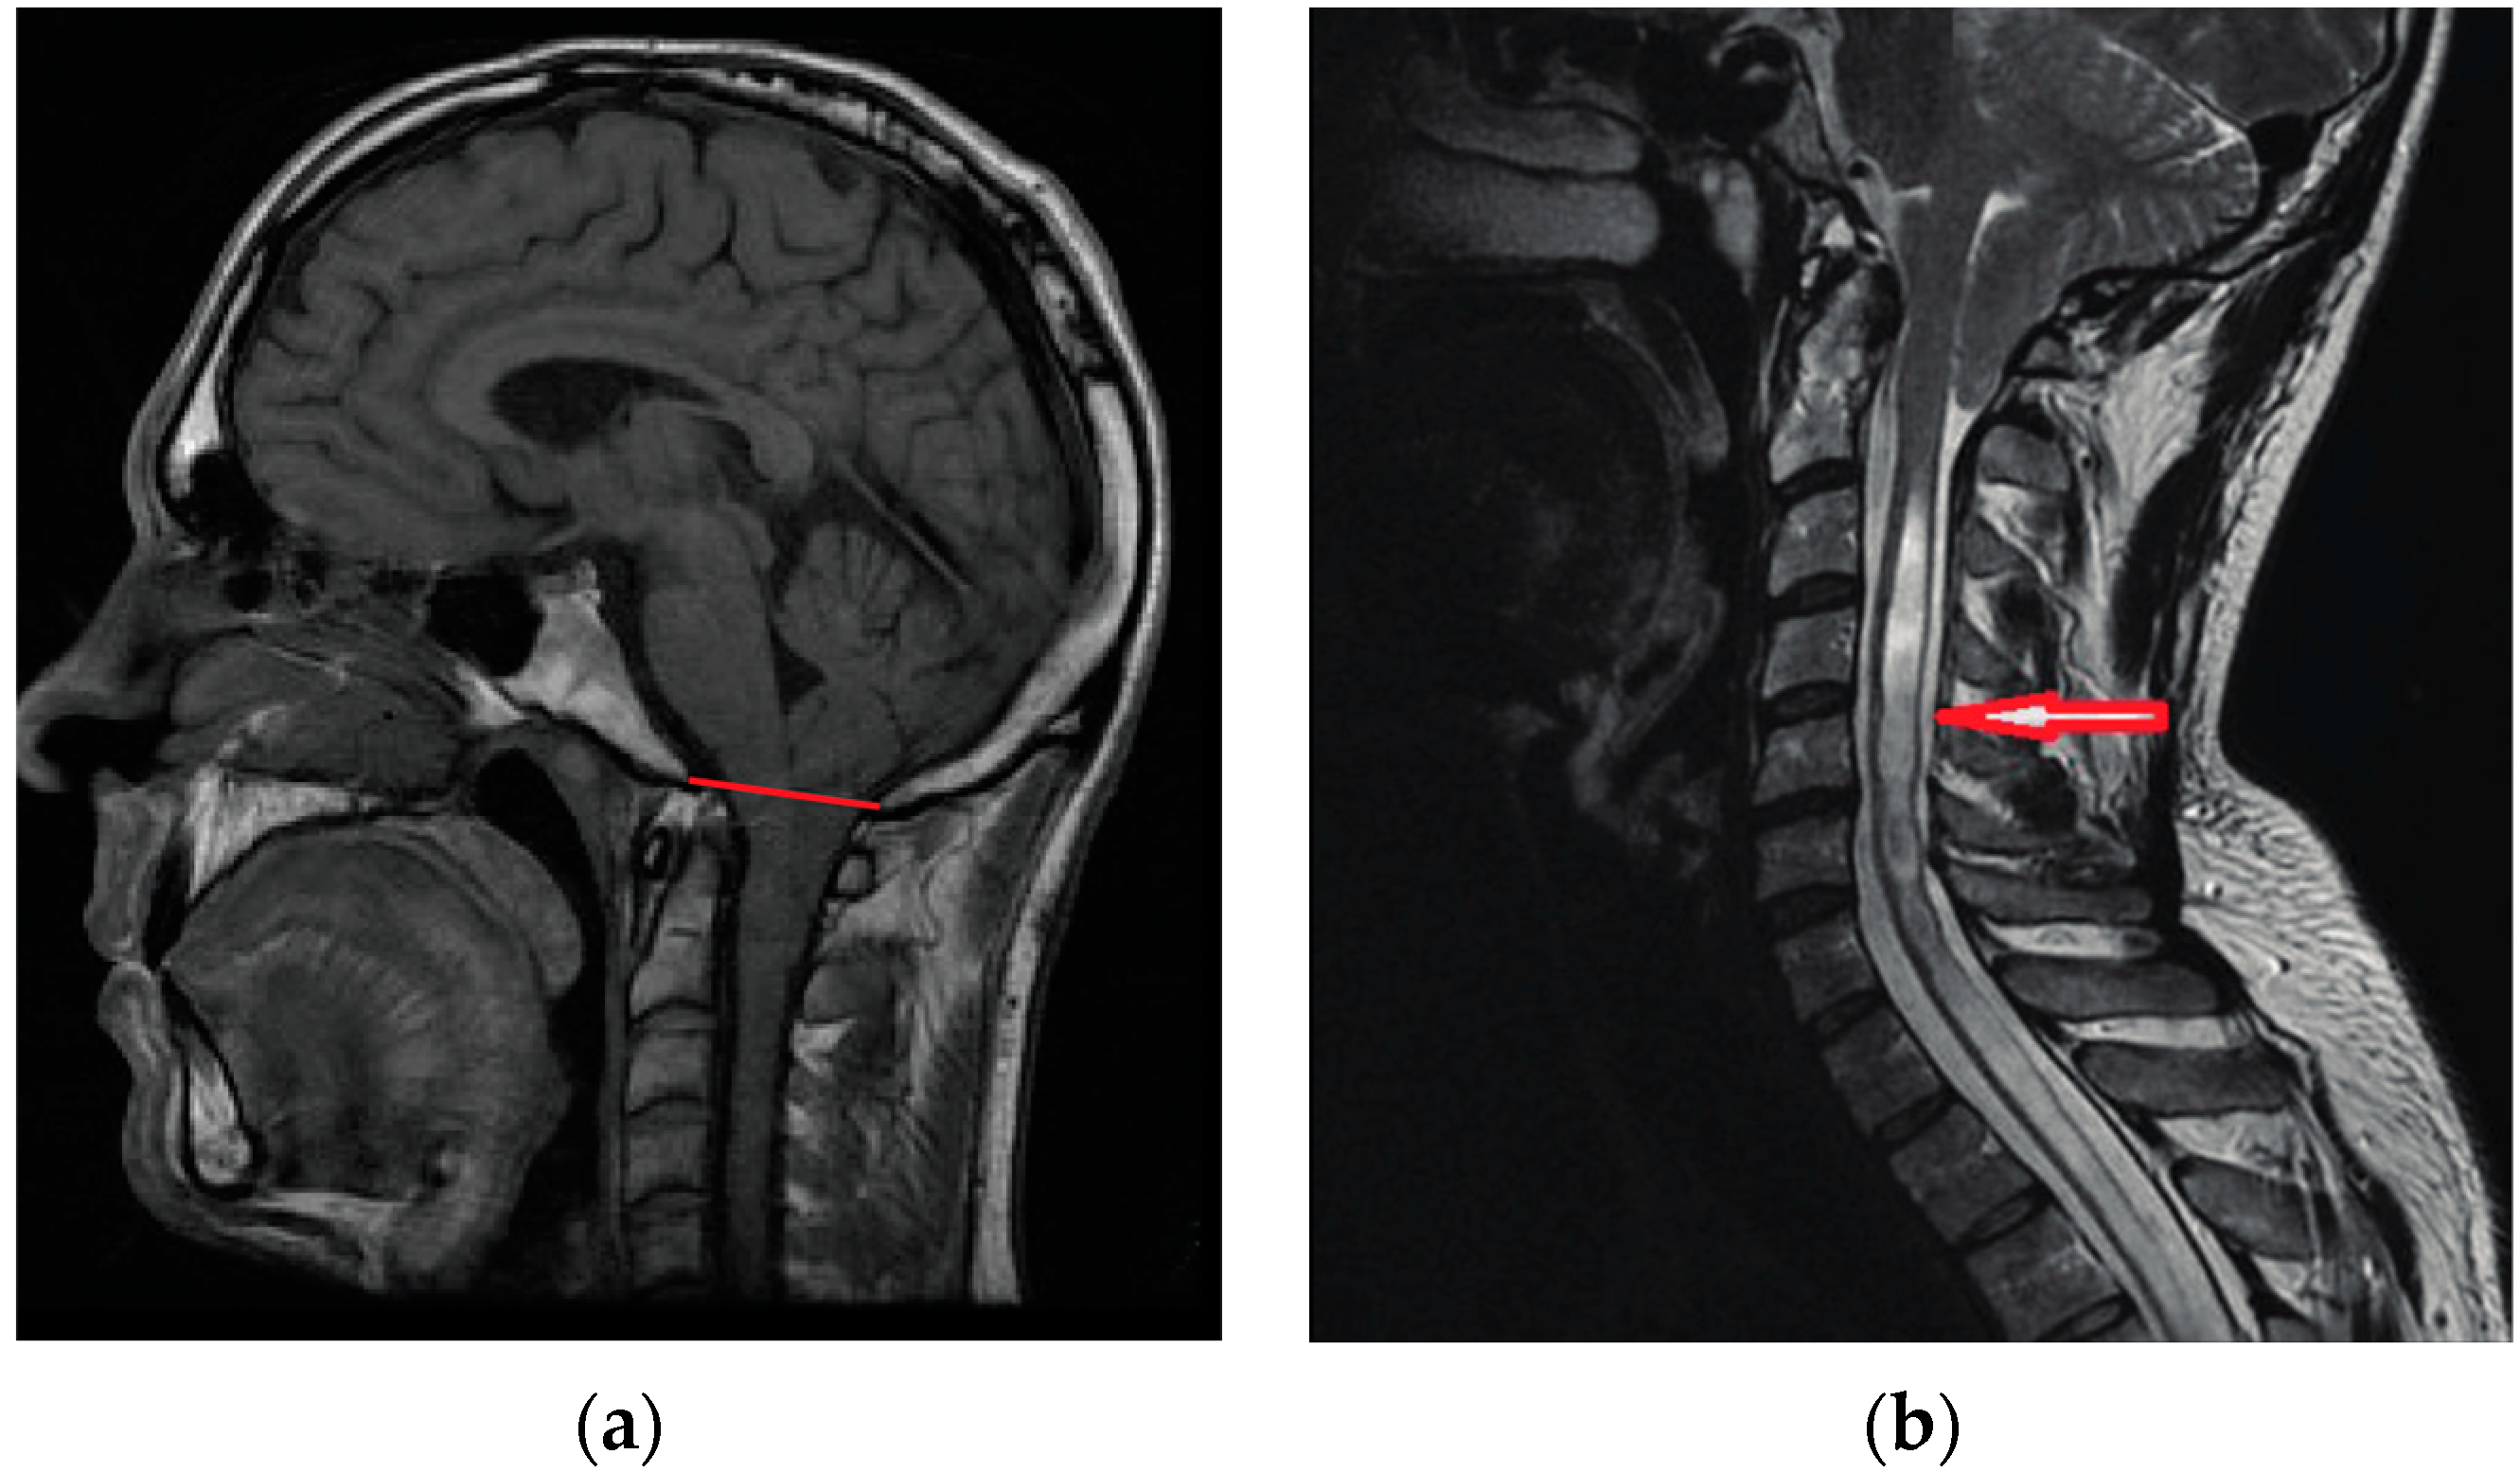

Chiari malformation type 1 (CM1) is characterized by a caudal displacement of the cerebellar tonsils below the foramen magnum at the base of the skull [1,2], and is classified among cerebellar dysplasias (Q07; ORPHA268882). It is diagnosed primarily by magnetic resonance imaging (MRI) and is defined as the herniation of the cerebellar tonsils greater than five millimeters below the basion–opisthion line (i.e., McRae line) (Figure 1a). Many cases often also have skull morphometric variations, such as short clivus and craniovertebral junction [3]. Symptomatology varies between patients and severity is not necessarily correlated with the extent of tonsillar displacement [2,4]. According to epidemiological data, the prevalence of CM1 meeting imaging criteria is 7/100,000 of which 4.5/100,000 (58%) are asymptomatic [5,6,7]. Therefore, clinical history and features (neurological symptoms and signs) complete the clinical diagnosis of CM1. It is likely that brain compression and cerebrospinal fluid disturbances underlie symptoms. When symptoms persist, treatment aimed at symptom amelioration is primarily surgical, involving the decompression of the posterior fossa.

Figure 1.

Chiari 1 Malformation (CM1). Sagittal MRI (a) Male, 24 years; CM1 is defined as a displacement of the cerebellar tonsils greater than five millimeters below the basion–opisthion line (red line); (b) Female, 38 years; CM1 with long segment syringomyelia (red arrow).

The posterior fossa contains the cerebellum, pons, and medulla. It is bordered posteriorly by the occipital bone, laterally by the two temporal bones, and superiorly by the tentorium. The brainstem transitions into the spinal cord as it exits the posterior fossa through the foramen magnum, a large opening at the base of the skull. While the cerebellum is normally contained within the posterior fossa, the cerebellar tonsils herniate through the foramen magnum in CM1 (Figure 1).